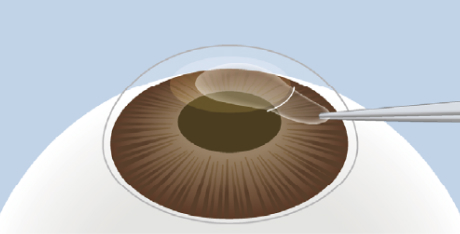

レンチクルの摘出

作成した切開部からレンチクルを丁寧に取り出します。これにより角膜の屈折力が変化し、視力が矯正されます。

自然治癒を待つ

縫合も不要で、

切開部は自然に癒合します。